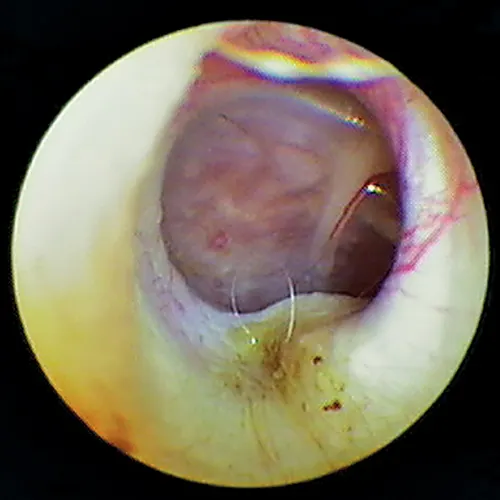

In some dogs, the pars flaccida of the eardrum may be bulging from fluid pressure in the middle ear behind it (Figure 16) and may obscure visualization of the pars tensa. Some have suggested that this enlargement may be caused by degranulation of mast cells and resultant edema from atopic dermatitis.7,8 This condition is frequently mistaken for a mass in the external canal and should be closely evaluated.

Otoscopic image of domed eardrum with hair and yellow exudate visible in internal ear canal.

FIGURE 16

Bulging eardrum caused by increased fluid pressure in the middle ear

In the Cavalier King Charles spaniel, a condition called primary secretory otitis media can cause bulging of the eardrum resulting from the failure of mucoid drainage from the tympanic bulla through the auditory tube.